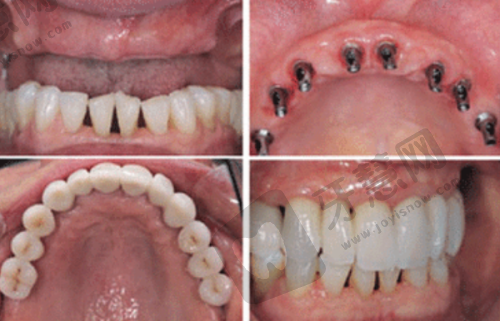

多方位诊疗服务:从基础的洁牙、补牙到复杂的牙齿矫正、种植牙、牙周病治疗等,都能提供多方位、个性化的诊疗方案。尤其在儿童口腔健康方面倾注大量心血,致力于降低6 - 18岁龋患率和错合畸形发病率。孩子们在治疗时能通过3D模拟动画提前预见矫治后的成效,提升了治疗过程的透明度和趣味性。

良好口碑见证:福州海狸家口腔门诊部凭借多店连锁的便捷性、技术可靠的专科性以及收费合理的亲民性,在福州口腔医疗领域树立了良好的口碑。许多家长表示,孩子在这里治疗后牙齿变整齐,面部美观改善,自信心得到提升。

顾客评价实例:顾客A称,孩子牙齿不整齐,医生特别专精,制定详细正畸方案,孩子戴牙套异物感低、不疼,半年过去牙齿有位移,复诊还提供校门口就诊服务;顾客B表示,带孩子做儿童早期干预矫正,医生推荐MRC肌功能训练,孩子不良习惯明显改善,环境干净,医护耐心解释治疗过程和注意事项,对治疗体验非常满意。